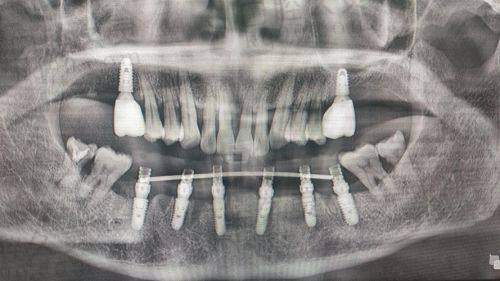

西宁市非凡口腔医院种植牙价格是多少,种植牙多少钱一颗:

西宁市非凡口腔医院韩国登腾种植体:2380元起/颗

西宁市非凡口腔医院韩国奥齿泰种植体:4800元起/颗

西宁市非凡口腔医院美国皓圣种植体:6600元起/颗

西宁市非凡口腔医院以色列科特斯种体:7500元起/颗

西宁市非凡口腔医院瑞士iti种植体:9800元起/颗

西宁市非凡口腔医院德国种植体:10000元起/颗

西宁市非凡口腔医院瑞典诺贝尔种植体:13000元起/颗

从西宁市非凡口腔医院种植牙价格表中可以看出,单颗种牙的价格是2380-13000元左右,可以看出韩国登腾种植体仅需2380元左右,性价比比较高,瑞典、以色列、美国种植体的价格稍微偏高一点,但是已经是今年的集采价格了,非常划算,种植牙的价格仅供参考,实际价格以到院面诊为准!